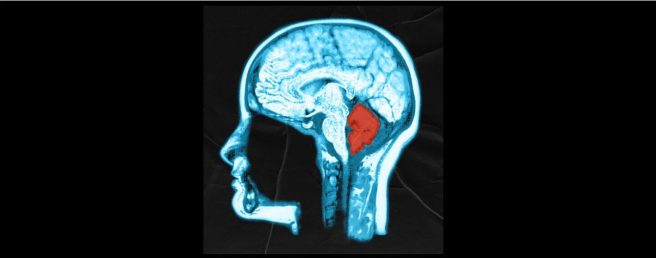

4. The cerebellum and dykinesias

Here’s one for the “Cerebellum has nothing to do with Parkinson’s” crowd: The cerebellum is a structure at the back of your head, located just inside your skull above your next. It is a large pair of lobes, but for a long time it has been considered as having no role in Parkinson’s. Now researchers have demonstrated that short trains of stimulation of cerebellar Purkinje neurons was “sufficient to suppress Levodopa-induced dyskinesia or even prevent their development” (in mice – click here to read more about this).

- New review explores pathological, structural, & functional changes of the cerebellum in Parkinson’s & discusses the role of the cerebellum in PD-related tremor, with the aim of providing an overview of the cerebellum-related mechanism of tremor in PD (Click here to read more about this).